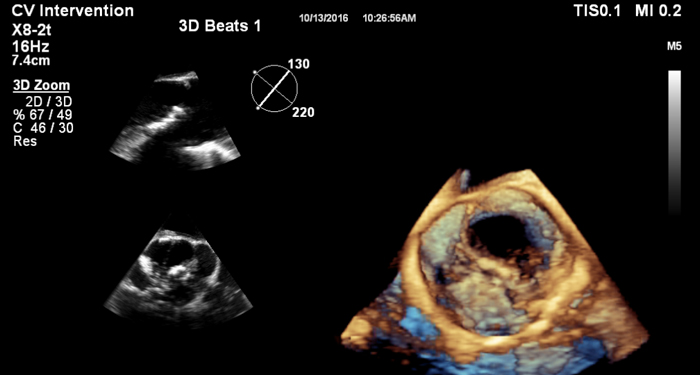

At the touch of a button, the new MaxVue high-definition display brings extraordinary visualisation of anatomy with 1,179,648 additional image pixels compared to a standard 4:3 display format mode. MaxVue enhances ultrasound viewing during interventional procedures and provides 38% more viewing area to optimise the display of dual, side/side, biplane, and scrolling imaging modes.

MaxVue offers a 38% greater viewing area.

MaxVue offers 1,179,648 additional image pixels compared to a standard 4:3 display format mode.